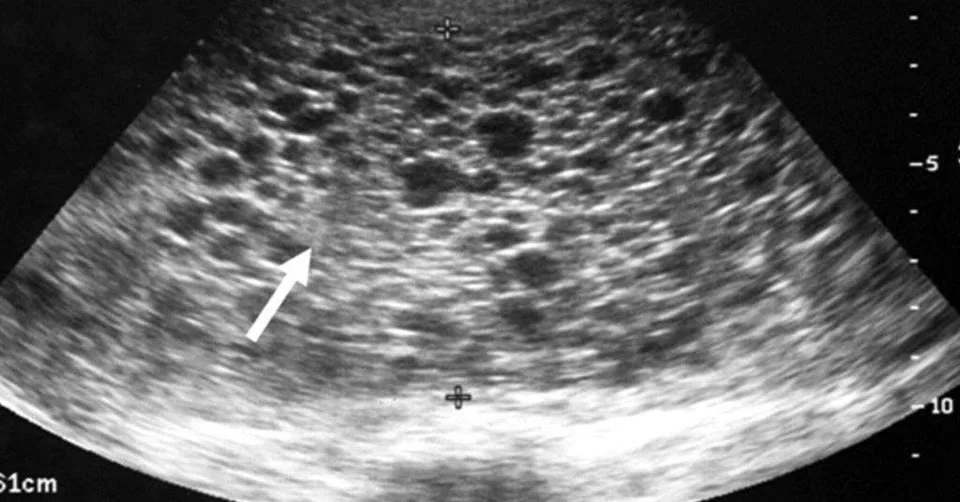

-Kehamilan anggur boleh dikesan melalui ultrasound, di mana gugusan tisu berbentuk anggur dapat dilihat dan janin tidak dapat dikesan.